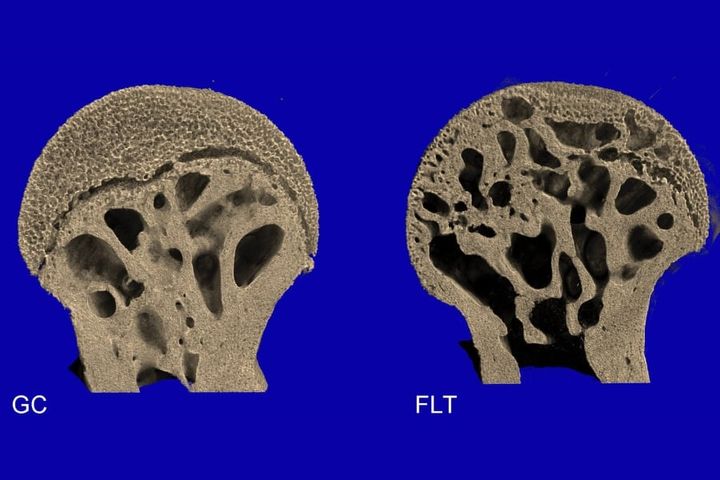

分析の結果、宇宙に滞在したマウスの大腿骨では、内部のスポンジ状の骨が大きく失われていたのです。

特に股関節や膝に近い部位では、骨密度が大幅に減っており、大きな空洞が広がっていました。

一方で、脊椎の腰椎部分ではほとんど変化が見られませんでした。

左:地上のマウスの大腿骨、右:ISSのマウスの大腿骨/ Credit: Rukmani Cahill et al., PLOS ONE(2025)

今回の研究結果が示すのは、微小重力下での骨の弱体化は全身に均等に起こるのではなく、荷重を支えている部位に集中することが示されました。